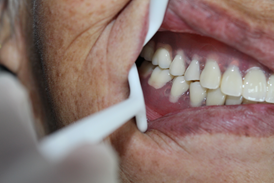

患者,女性,73歲。

主訴:多牙體缺失,余留牙體松動(dòng)不適,進(jìn)食效率低下(困難),要求治療。

治療方案:完善相關(guān)化驗(yàn)檢查,松動(dòng)牙拔除,并行全口種植桿卡修復(fù)治療。

術(shù)前片/術(shù)后片

咬合確定 /治療結(jié)束